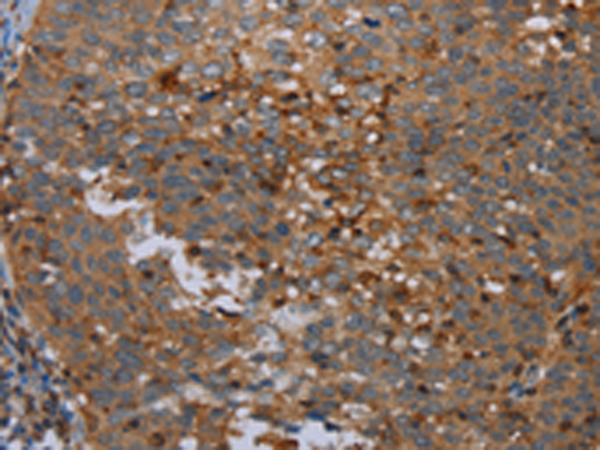

分类: 科研抗体货号: P05052别名: HIP; PAP; PAP1; REG3; INGAP; PAP-H; PBCGF; HIP/PAP; REG-III应用: WB,IHC反应种属: Human

分类: 科研抗体货号: P04998别名: CT31; PLU1; PUT1; PLU-1; JARID1B; RBBP2H1A应用: IHC反应种属: Human, Mouse